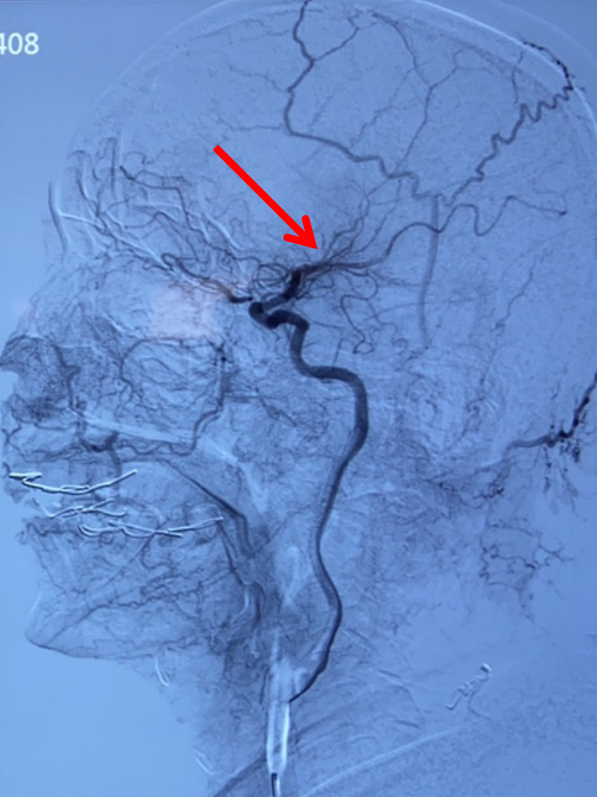

右侧颈总动脉侧位造影:右侧大脑中动脉M2上干、下干均闭塞(箭头示)。

再次造影证实右侧大脑中动脉上干、下干均闭塞(箭头示)。